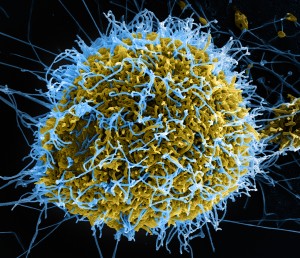

Bioinspired coating for medical devices avoids clotting and suppresses bacterial infection

Repels blood and bacteria, including biofilms